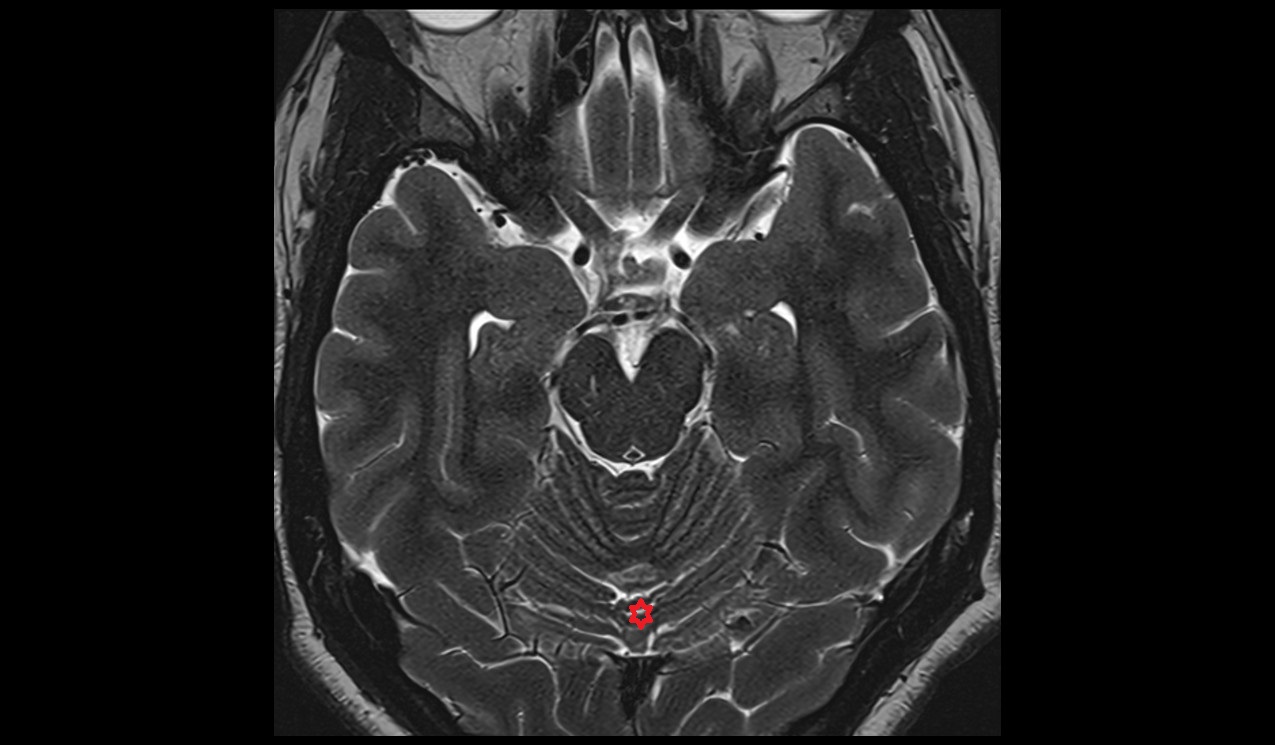

- Cerebellum

- Tonsil of cerebellum

- Posterior cerebellomedullary cistern (cisterna magna)

- Cisterna magna